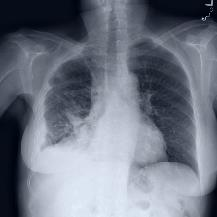

Thoracic disease detection from chest radiographs using deep learning methods has been an active area of research in the last decade. Most previous methods attempt to focus on the diseased organs of the image by identifying spatial regions responsible for significant contributions to the model's prediction. In contrast, expert radiologists first locate the prominent anatomical structures before determining if those regions are anomalous. Therefore, integrating anatomical knowledge within deep learning models could bring substantial improvement in automatic disease classification. This work proposes an anatomy-aware attention-based architecture named Anatomy X-Net, that prioritizes the spatial features guided by the pre-identified anatomy regions. We leverage a semi-supervised learning method using the JSRT dataset containing organ-level annotation to obtain the anatomical segmentation masks (for lungs and heart) for the NIH and CheXpert datasets. The proposed Anatomy X-Net uses the pre-trained DenseNet-121 as the backbone network with two corresponding structured modules, the Anatomy Aware Attention (AAA) and Probabilistic Weighted Average Pooling (PWAP), in a cohesive framework for anatomical attention learning. Our proposed method sets new state-of-the-art performance on the official NIH test set with an AUC score of 0.8439, proving the efficacy of utilizing the anatomy segmentation knowledge to improve the thoracic disease classification. Furthermore, the Anatomy X-Net yields an averaged AUC of 0.9020 on the Stanford CheXpert dataset, improving on existing methods that demonstrate the generalizability of the proposed framework.